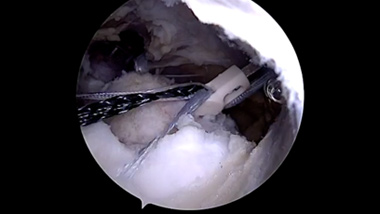

Rotator cuff repair is a surgery to repair an injured or torn rotator cuff. It is usually performed arthroscopically on an outpatient basis. An arthroscope, a small, fiber-optic instrument consisting of a lens, light source, and video camera. The camera projects images of the inside of the joint onto a large monitor, allowing your doctor to look for any damage, assess the type of injury and repair it. Large rotator cuff tears may require open surgery.

- An arthroscope is inserted through the incision.

- Miniature surgical instruments are inserted to remove the damaged part of the tendon and injured surrounding tissue.

- The damaged ends of the tendon are sewn together. Care is taken to prevent damage to nearby nerves or blood vessels.

- A suture anchor may be used to reattach a completely torn tendon to the bone.